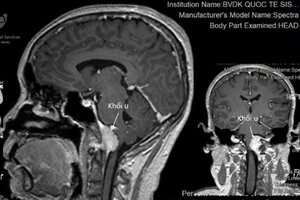

Tưởng chóng mặt do rối loạn tuần hoàn, té ra bị u não hiếm gặp